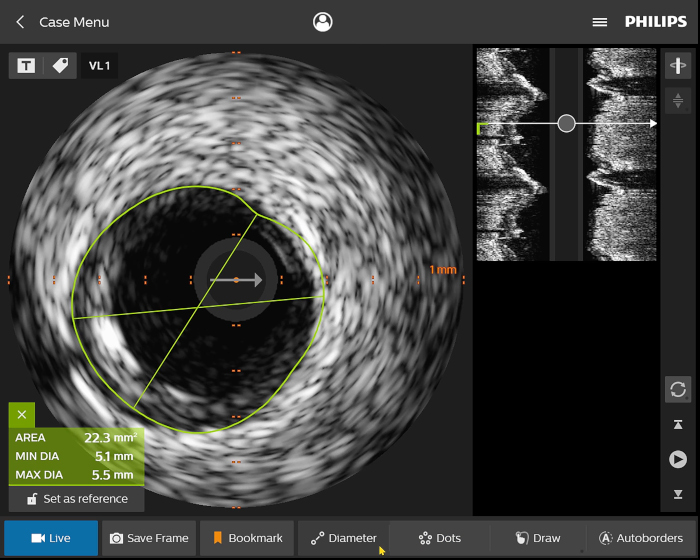

Presentamos la nueva plataforma de aplicaciones intervencionistas Philips IntraSight, en la que la imagen, la fisiología, el corregistro* y el software se unen para facilitar una atención óptima del paciente. IntraSight ofrece un conjunto completo de modalidades clínicamente probadas, como la iFR/FFR, la IVUS y el corregistro* para simplificar las intervenciones complejas, acelerar los procedimientos rutinarios y proporcionar una mejor atención al paciente.

Construida sobre una plataforma inteligente basada en aplicaciones que puede escalar para satisfacer las necesidades cambiantes de su laboratorio cuando se disponga de nuevas aplicaciones o modalidades, sin necesidad de adquirir nuevo hardware. Solo Philips IntraSight ofrece las mejores herramientas de imagenología y fisiología de su clase con iFR, corregistro iFR*, FFR, IVUS, corregistro IVUS* y Angio+*. Con su arquitectura modular, IntraSight se mantiene a la vanguardia de los últimos avances y actualizaciones de seguridad importantes.

Figura 1